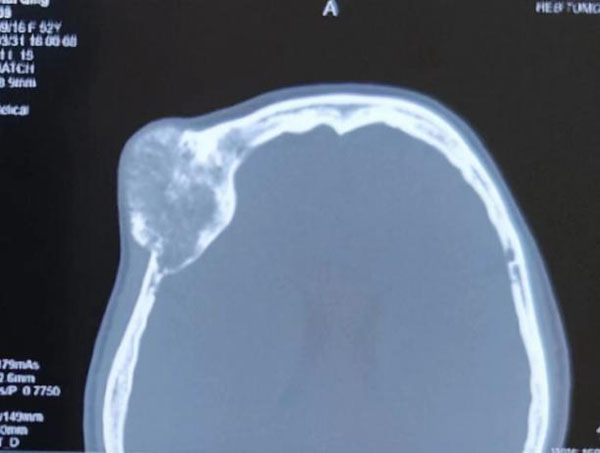

患者主因右眼視物不清伴眼球突出3年,以右眼眶內(nèi)占位收入我院眼科。眼科郝玉華教授在檢查中發(fā)現(xiàn),患者右眼視力極低,右眼上瞼下垂,眼球突出且運動明顯受限。眼眶CT提示眶內(nèi)巨大占位,幾乎占據(jù)球后整個眶間隙。同側(cè)額部顱骨骨質(zhì)亦顯示巨大腫瘤,約7*7 cm大小。患者已經(jīng)有上瞼下垂和視力明顯下降的癥狀,表明腫物已經(jīng)對眶上裂神經(jīng)和視神經(jīng)有一定壓迫。